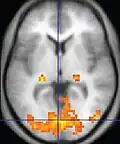

Neuroimagem

A ressonância magnética é a ferramenta investigativa de escolha para cânceres neurológicos, pois tem melhor resolução do que a TC e oferece uma melhor visualização da fossa posterior. O contraste fornecido entre matéria cinza e branca torna a ressonância magnética melhor opção para muitas condições do sistema nervoso central, incluindo doenças desmielinizantes, demência, doença cerebrovascular, doenças infecciosas e epilepsia.[30] Uma vez que muitas imagens são retiradas em milisegundos, mostra como o cérebro responde a diferentes estímulos, permitindo que os pesquisadores estudem as anormalidades cerebrais funcionais e estruturais em distúrbios psicológicos.[31] A RM também é utilizada na cirurgia estereotáxica guiada por MRI e radiocirurgia para o tratamento de tumores intracranianos, malformações arteriovenosas e outras condições tratáveis cirurgicamente usando um dispositivo conhecido como N-localizer.[32][33][34][35][36][37][38][39][40][41][42][43][44][45]

| Ressonância Magnética Funcional (fMRI) | Imagem dependente do nível de oxigênio no sangue | BOLD | Mudanças na magnetização dependente da saturação de oxigênio da hemoglobina refletem a atividade tecidual.[87] | Localização da atividade cerebral ao executar uma tarefa atribuída (por exemplo, falar, mover os dedos) antes da cirurgia, também usado na pesquisa de cognição.[88] |  |